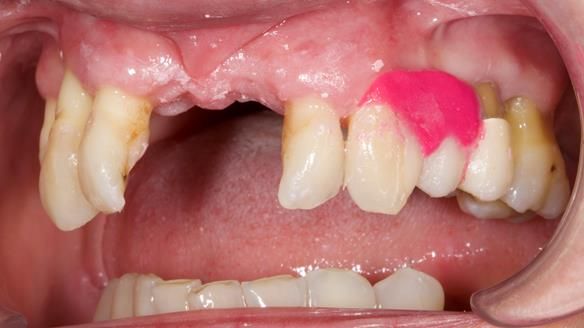

She had previously suffered from generalised periodontitis – stage IV, grade C, currently stable, with reduced attachment across the upper arch.

By the time she came to me, her periodontal condition was stable — but the aesthetics in the upper jaw were very poor.

Dr Syed Abad — my colleague and a Specialist in Periodontics — had successfully stabilised her gum health.

We provided her with an immediate upper denture (Mk 1), followed by a definitive metal-based upper denture (Mk 2). A lower removable partial denture was discussed, to be made only if needed once the upper treatment was complete. However, at review, this wasn’t necessary — Adnana had excellent neuromuscular control and function, even with a shortened dental arch (SDA).